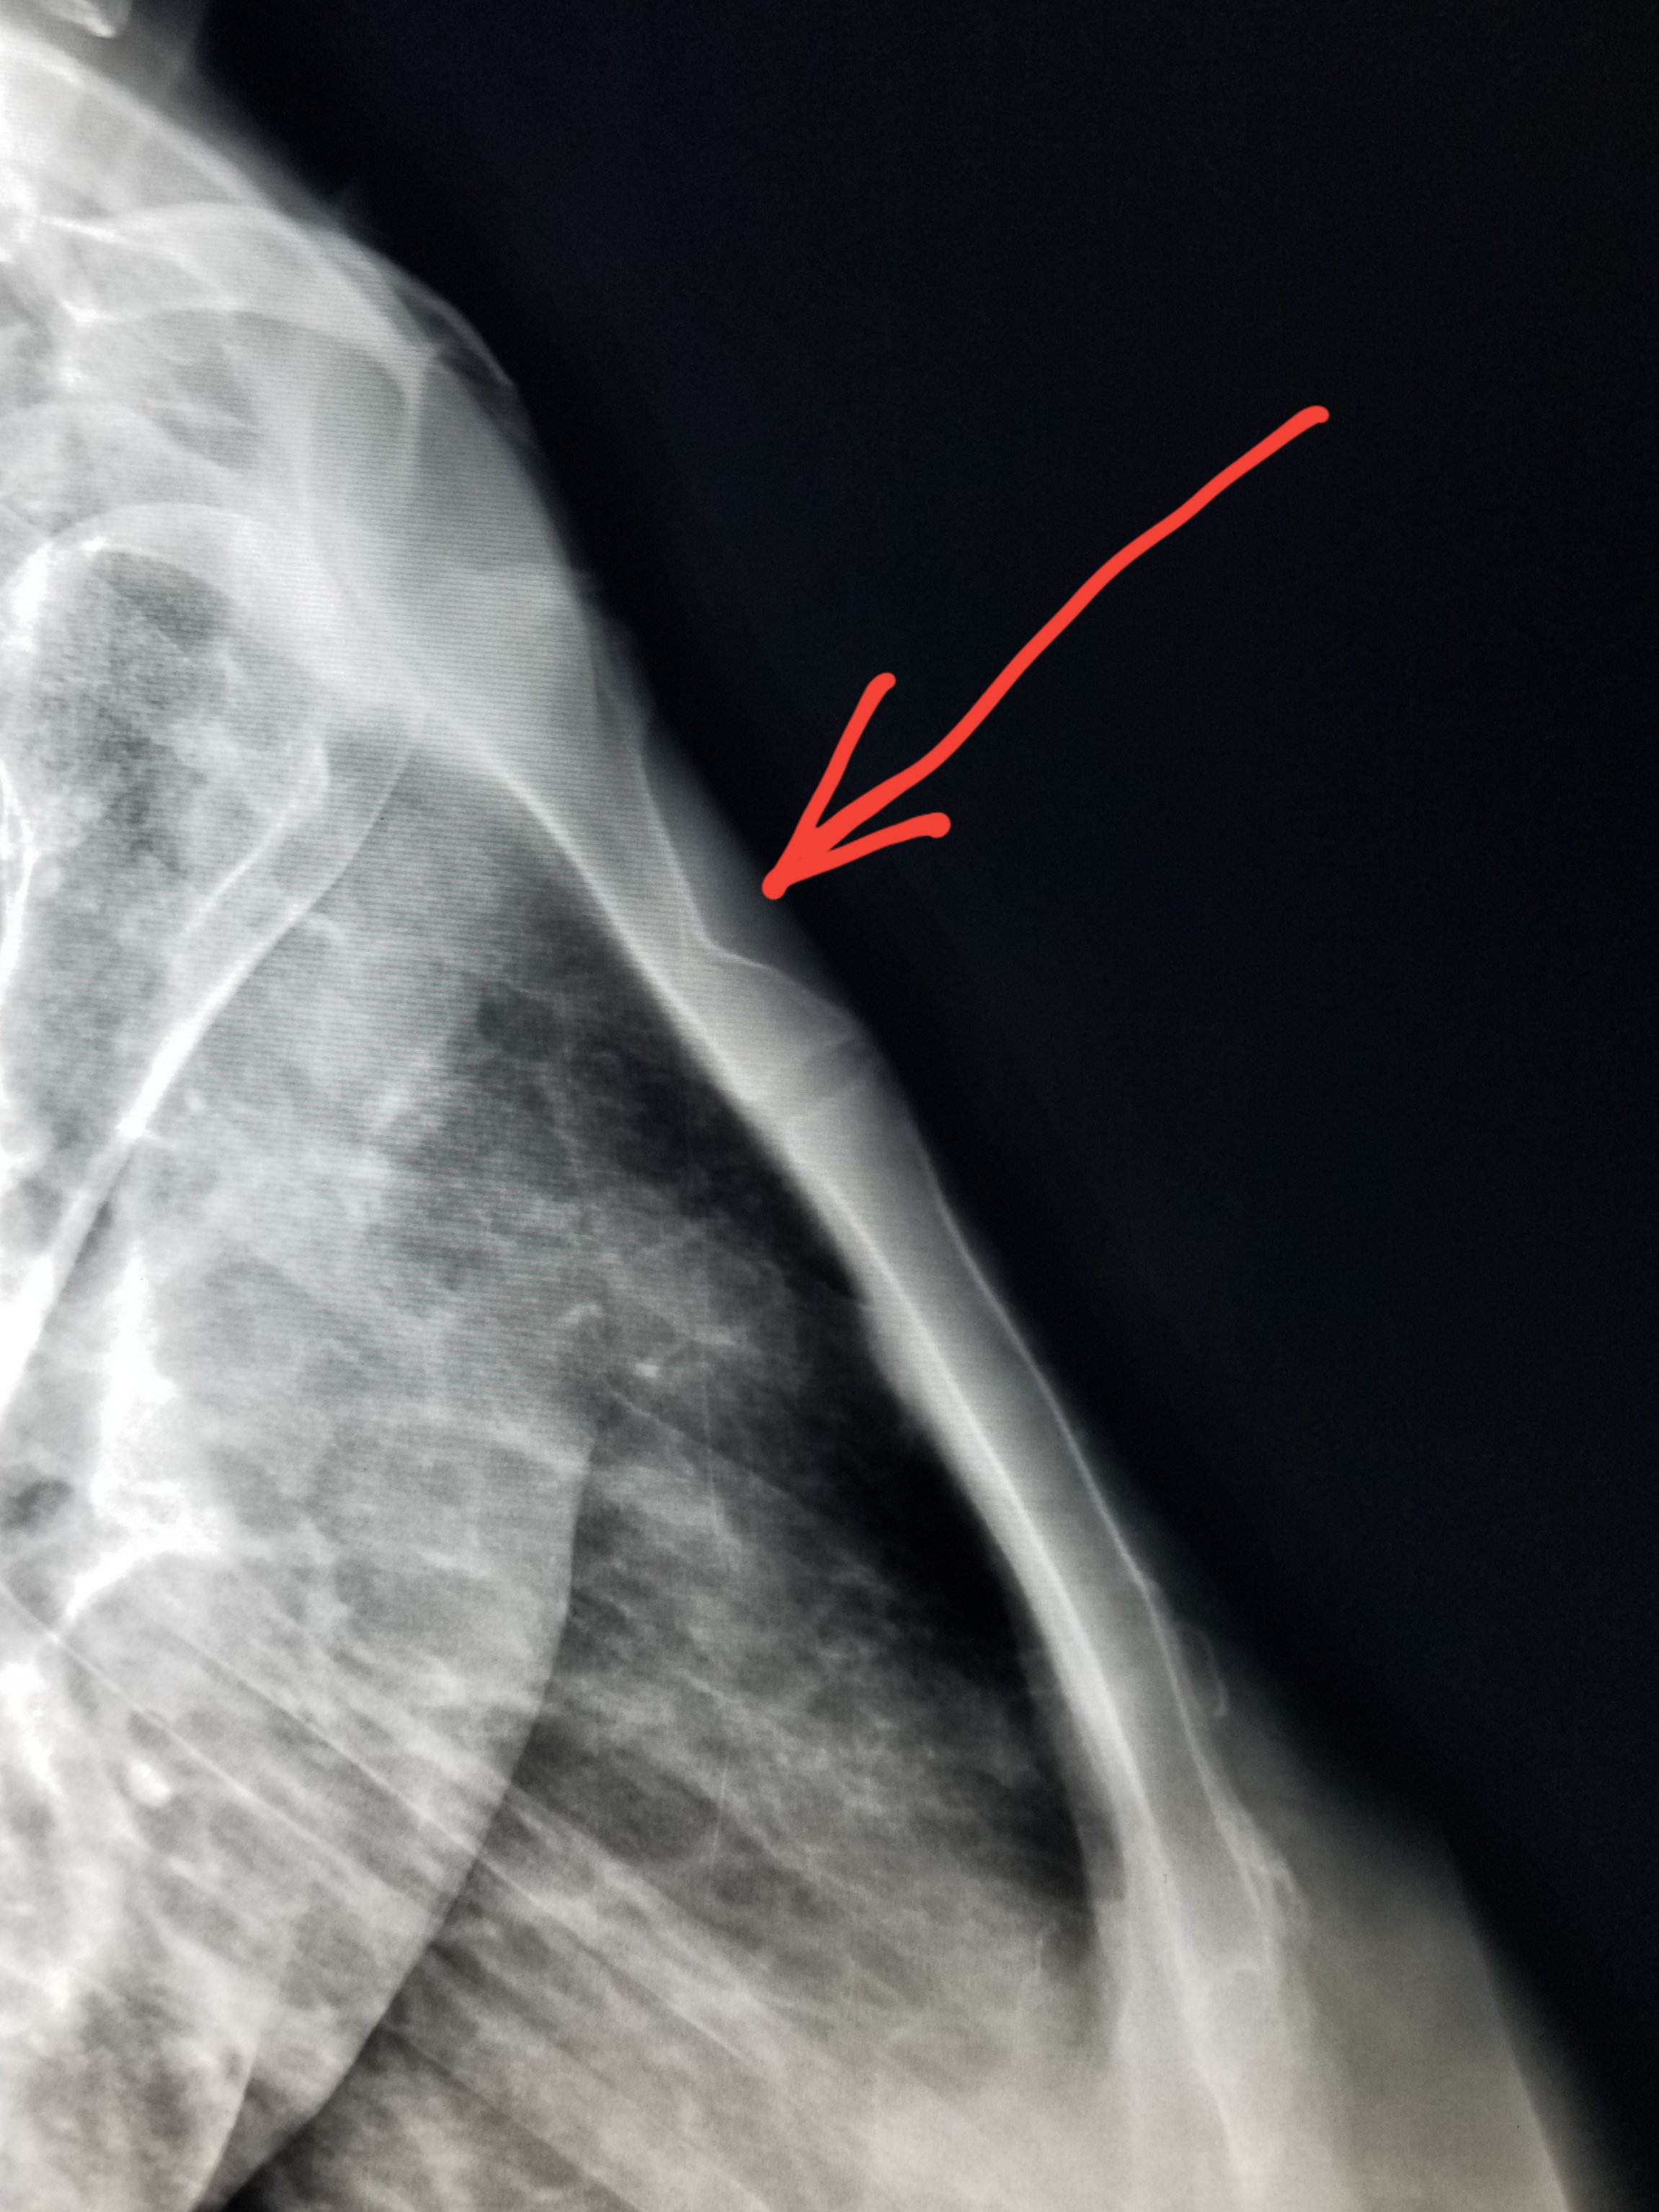

Sternum Fracture X Ray . sternal fractures are best detected on dedicated lateral sternal views as lucent cortical breaches with or without. Don't mistake the sternomanubrial junction for a fracture. Cardiopulmonary resuscitation (cpr) often results in sternal. The projection is performed rao to project the sternum over the homogenous heart. a lateral chest radiograph remains the gold standard investigation in diagnosing sternal fractures, as the. the lateral radiograph is usually the most valuable view for detecting sternal fractures and for determining the degree of displacement (see the. Fractures of the sternum are often due to. Look for a step in the cortex of the sternum. the patient is rao facing the upright detector;